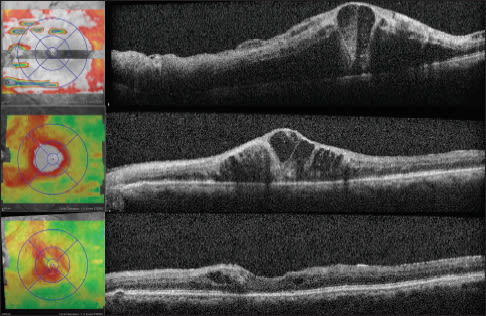

Case 2: Friends in Anterior Places. A 63-year-old female had been followed since March 2005 for a BRVO in her left eye. She had received focal laser and sector scatter laser in the same eye. Since that time, her VA was 20/200 in her right eye, with nuclear sclerotic cataracts and a macular scar. She had been followed annually until February 2009, when the SD-OCT appearance (Figure 3, top) prompted a trial of intravitreal bevacizumab injections for three months, with the resultant appearance (Figure 3, bottom) and visual acuity unchanged at 20/200. Subsequently, the patient was referred for cataract extraction and intraocular lens placement, and on most recent follow-up had a visual acuity of 20/60 on her examination.

Figure 3. Case 2: A 63-year-old female with BRVO in the left eye, followed for four years. SD-OCT suggests the presence of subretinal fluid under the macular scar (top), and prompted a series of intravitreal injections. After three injections the fluid is reduced (bottom), although the visual acuity is unchanged. Following cataract extraction and intraocular lens placement, the visual acuity was 20/60 on most recent follow-up.

The points of this case are that: (1) new treatments have changed the treatment paradigm for RVO patients; (2) the SD-OCT appearance seemed to suggest the presence of subretinal fluid and prompted a series of injections without functional benefit; and (3) the SD-OCT may have even “distracted” the examiner from addressing a treatable cause of decreased vision earlier on and before exposing the patient to the risks of intravitreal injections.

Case 3: A Stitch in Time. A 73-year-old male was referred in May 2010 by an outside retina specialist for treatment of CRVO in both eyes. The right CRVO had occurred in February 2010 and had received two previous bevacizumab injections, and the left CRVO had occurred in April 2010 and had received one bevacizumab injection. On presentation, VA was 20/100 in both eyes, and the examination showed findings consistent with the presenting diagnosis, with SD-OCT confirming CME in the right eye and a relatively compact retina in the left eye (Figures 4 and 5, top) Especially because of the subjective and objective visual acuity, the patient subsequently received subsequent bilateral bevacizumab injections over the next two months. In July 2010, the visual acuity was 20/60 in the right eye and 20/50 in the left eye. The SD-OCT appearance (Figures 4 and 5, middle) demonstrated persistent CME in the right eye, and the same compact appearance to the left macula. Because of the visual improvement and lack of obvious CME on SD-OCT, treatment was deferred for the left eye, though continued for the right eye.

Figure 4. Case 3: A 73-year-old male with bilateral CRVO and CME. SD-OCT shows CME in the right eye (top) with a VA of 20/70. After two injections of Avastin, there was less subretinal fluid (middle) and VA was 20/60. After continued treatment, there was persistent CME and VA was still 20/60. However, after three more injections, the CME decreased, and VA was 20/40.

Figure 5. Case 3: SD OCT shows a relatively compact retina in the left eye (top) with a visual acuity of 20/70, and a similar appearance after two intravitreal injections of Avastin (middle) although a VA of 20/50. Treatment was then deferred, but one month later CME reaccumulated and VA dropped to 20/100 (bottom). After continued treatment, the CME decreased and VA was 20/50.

Four weeks later, the patient returned with a visual acuity of 20/60 in the right eye and 20/100 in the left eye, and SD-OCT demonstrating persistent CME in the right eye and new intraretinal fluid in the left eye (Figures 4 and 5, bottom). Bilateral intravitreal bevacizumab injections were performed, and continued monthly until most recent follow-up in March, 2011, when visual acuity was 20/40 in the right eye and 20/60 in the left eye. Bilateral intravitreal bevacizumab injections were performed and were continued monthly until the most recent follow-up in March 2011, when the patient's VA was 20/40 in the right eye and 20/60 in the left eye.

This case illustrates that as-needed dosing, based on visual stability and OCT retinal thickness, may be initially detrimental to VA and may potentiate a longer duration of visual recovery. On the most recent follow-up, this patient had not yet regained the VA originally achieved after consecutive, initial monthly injections in the right eye after just a single month's break. In contrast, the left eye had continued to gain ground and allowed the patient to return to the level needed for legal driving privileges.